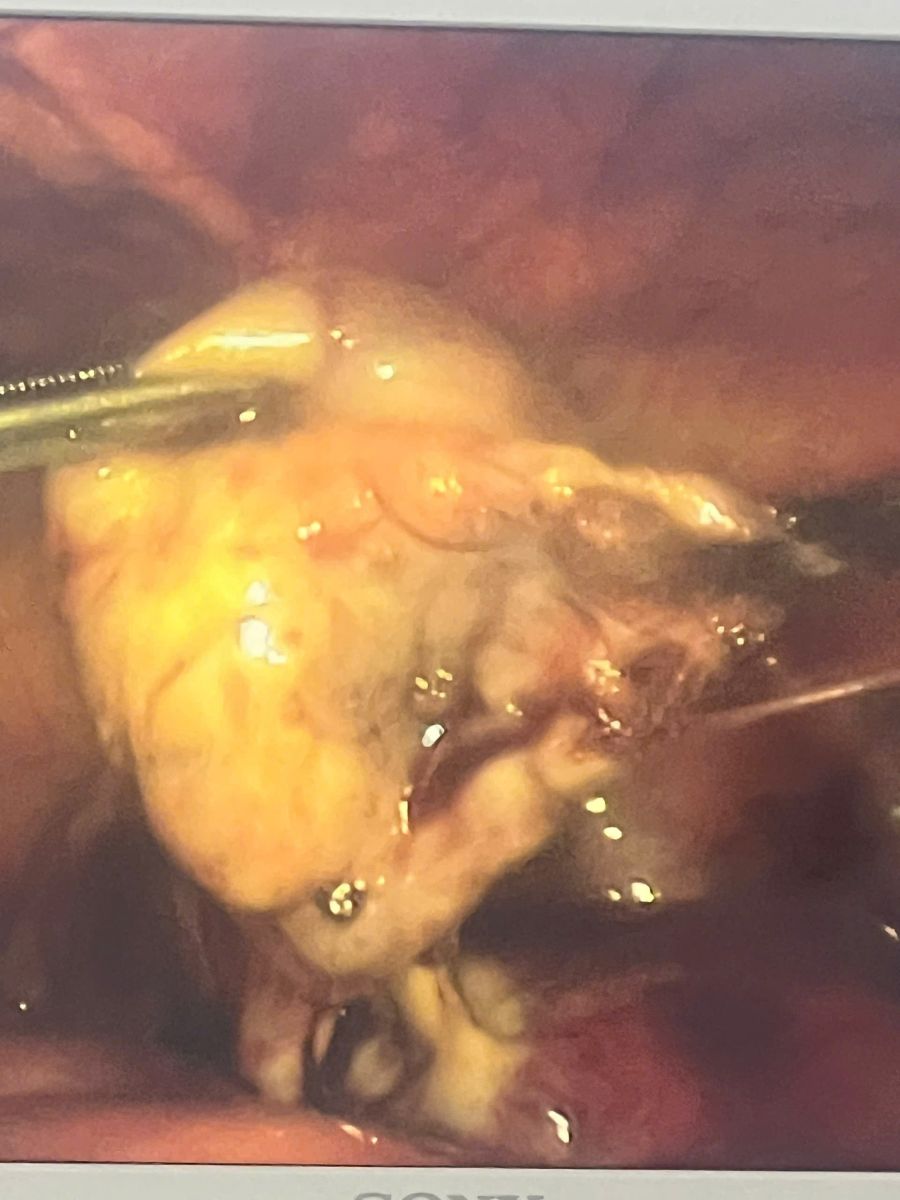

Kết quả chẩn đoán xác định bệnh nhân bị viêm ứ mủ vòi trứng. Đây là một tình trạng nhiễm trùng nặng khiến vòi trứng bị tắc nghẽn và ứ đọng dịch mủ bên trong. Nếu không được can thiệp kịp thời, khối mủ có thể vỡ gây viêm phúc mạc toàn bộ, áp xe vùng chậu, đe dọa trực tiếp đến tính mạng và để lại di chứng nặng nề cho sức khỏe sinh sản.

Ban đầu, bệnh nhân được điều trị nội khoa tích cực (dùng thuốc) trong 3 ngày. Tuy nhiên, do khối viêm lớn và tình trạng không thuyên giảm, các bác sĩ đã tiến hành hội chẩn chuyên môn và chỉ định phẫu thuật nội soi để xử lý triệt để ổ nhiễm trùng.

Ê-kíp phẫu thuật do BSCKII Nguyễn Đức Huân – Phó Giám đốc phụ trách chuyên môn trực tiếp làm phẫu thuật viên chính cùng các cộng sự đã thực hiện ca mổ an toàn và thành công. Nhờ sử dụng phương pháp phẫu thuật nội soi ít xâm lấn, ca mổ đã mang lại nhiều lợi ích cho bệnh nhân: